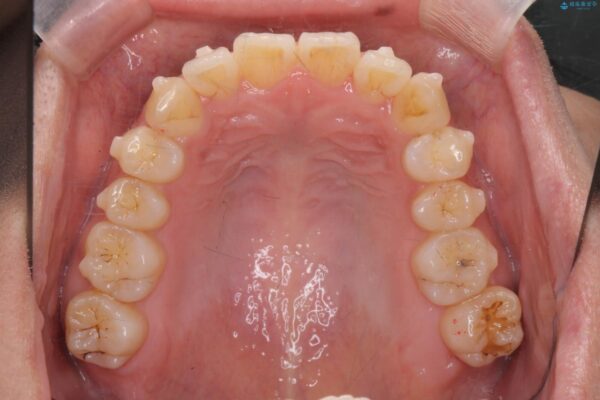

治療前

気になる犬歯のガタつきをマウスピース矯正で改善 治療前画像 気になる犬歯のガタつきをマウスピース矯正で改善 治療前画像 気になる犬歯のガタつきをマウスピース矯正で改善 治療前画像 気になる犬歯のガタつきをマウスピース矯正で改善 治療前画像